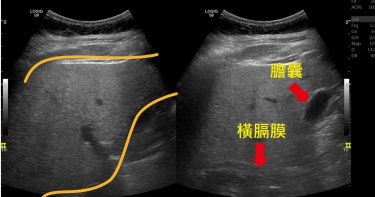

62歲的何先生(化名)是科技公司高階主管,長期拼酒以及愛吃高糖、油炸等高熱量食物,進行體檢竟發現逼近重度肥胖,而且肝功能、血脂肪、血糖和尿酸都出現紅字,不僅有重度脂肪肝,甚至出現中度肝纖維化!中國醫藥大學附設醫院健康醫學中心健康檢查科主任陳毓隆指出,何先生的脂肪堆積在肝臟,引發慢性肝臟發炎,擔心再這樣下去,中度肝纖維化恐惡化形成肝硬化。何先生有肥胖、高血壓和睡眠呼吸中止症病史,本身熱愛美食,也經常和客戶應酬,肚子越來越圓,體重直線上升到98公斤。由於海外駐點時間較長,他趁著放長假回台進行體檢,一檢查竟然發現,肥胖指標的身體質量指數(BMI)一年內從32上升到34.2,逼近重度肥胖35,而且肝功能、血脂肪、血糖和尿酸都出現紅字,照腹部超音波則發現了重度脂肪肝,進行肝纖維掃描甚至出現中度肝纖維化,令他驚覺健康亮紅燈!2條黃色線內是肝臟的範圍,肝臟因堆積較多脂肪,導致超音波下肝臟是白花花一片,箭頭處為膽囊與橫膈邊界變得模糊,是重度脂肪肝的影像表現。(圖/中國醫藥大學附設醫院提供)中醫大附醫健康醫學中心健康檢查科主任陳毓隆呼籲,民眾透過定期健康檢查掌握自身是否肥胖,早期發現,早期治療,半年內以減去原體重 5-10%為初步目標。(圖/中國醫藥大學附設醫院提供)半年狂甩5公斤肥油 紅字消退中何先生大為緊張,下定決心減重,遵照醫師開出的運動與飲食指引,每周至少去健身房3次,在健身教練指導下努力進行重訓,在家則改吃高纖低熱量的食物。經過半年的努力,何先生成功甩掉5公斤肥肉,血壓、血糖、血脂肪與尿酸指標也有明顯改善,精神與體力都大幅改善中。放任肥胖恐拖成重症! 當心7類疾病上門中醫大附醫健康醫學中心副院長林文元指出,肥胖合併多重健康危機,放任肥胖帶來的健康影響,小病拖成重症,帶來不可逆的遺憾,需高度警戒。衛生福利部最新公布111年國人十大死因統計,除了新冠疫情的死亡外,以高血壓性疾病(10.6%)、心臟疾病(8.3%)及糖尿病(7.3%)等3項疾病的死亡漲幅最多,而這3項疾病都與肥胖關係密切。根據台灣2017-2020年「國民營養健康狀況變遷調查」顯示,成人過重及肥胖盛行率達到50.3%,增加多種疾病甚至癌症的罹病風險。高血壓糖尿病心血管疾病脂肪肝睡眠呼吸中止症胃食道逆流癌症陳毓隆呼籲民眾透過定期健康檢查掌握自己是否罹患肥胖相關疾病,早期發現、早期治療,初步目標為半年內以減去原體重5-10%,通常減3-5%並維持即可見臨床指標改善,民眾不妨找家庭醫學科醫師或營養師諮詢減重細部飲食指引與運動處方。